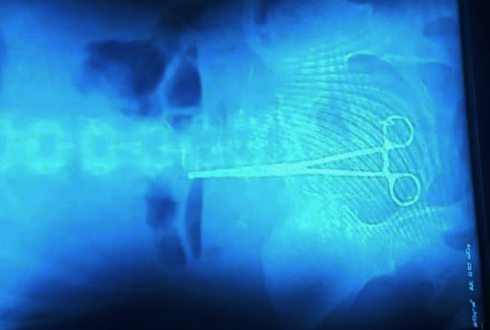

"ექიმებს ოპერაციის დროს მაკრატელი მუცელში დარჩათ" [video]

მაკრატლის ამოსაღებად გოგოს რუსთავში ოპერაცია ამ წუთებში უტარდება